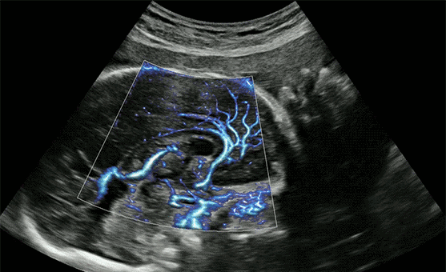

CrystalLive?是三星最新的超聲成像引擎,同時(shí)增強(qiáng)了2D圖像處理能力、3D渲染能力和彩色信號處理能力,能夠在復(fù)雜情況下提供出色的圖像性能,具備檢測外周血管、微循環(huán)血流的能力。

2D成像方面,Hera i10集成了包括ShadowHDR?、HQ-Vision?、ClearVision等多項(xiàng)具有三星“血統(tǒng)”的技術(shù),加強(qiáng)了圖像的陰影抑制、減少偽影、緩和模糊區(qū)。